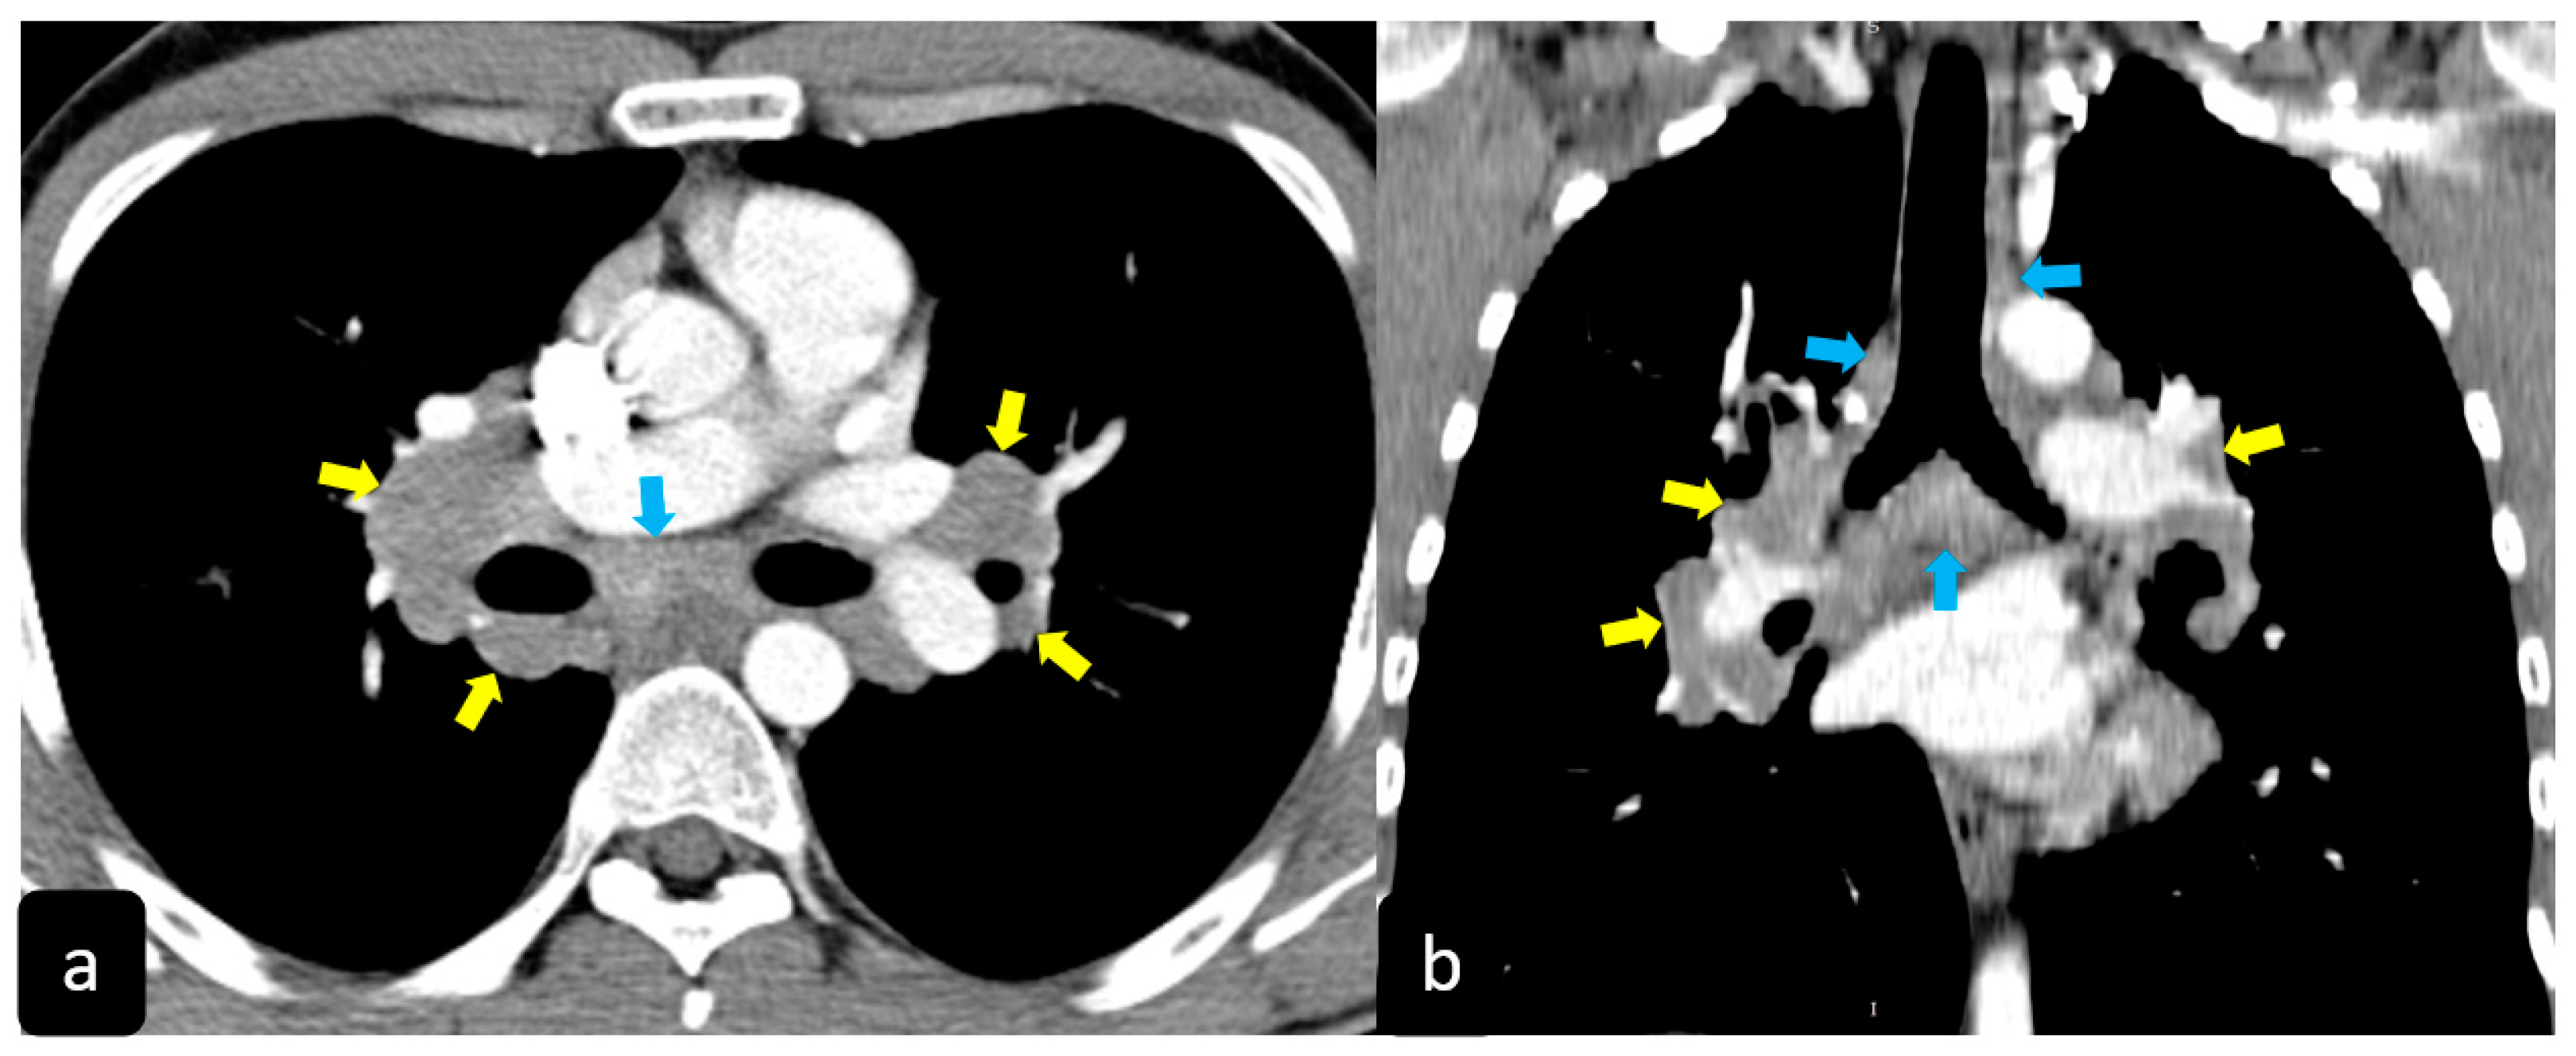

High resolution computed tomography (HRCT) has a higher sensitivity than the chest X-ray and lymph node enlargement, commonly with a size of 2–5 mm, and the specific impairment of lungs are visualized more in detail. Parenchymal involvement can be minimal or characterized by bilateral parenchymal infiltrates that tend to merge into large and irregular pulmonary opacities. The most common and important parenchymal finding is the presence of micronodules (granulomas; 2–4 mm in diameter; well defined and bilateral) with a typical perilymphatic distribution along the peribronchovascular and subpleural interstitial space and interlobular septa (Figure 1a’ and Figure 2). CT is more sensitive than the chest x-ray in the identification of characteristic hilar (Figure 3a) and mediastinal (Figure 3b) lymphadenopathy [3]. A wide variety of less specific alterations can be found, such as unilateral or isolated lymphadenopathy, solitary nodules, confluent alveolar opacities, (the so-called alveolar sarcoid pattern), linear opacities, conglomerate masses, thickened interlobar septa, cysts, blebs, isolated bullae, or diffuse emphysema (Figure 4). Another typical imaging finding of sarcoidosis is the galaxy sign, a mass-like lesion, composed of numerous smaller coalescing granulomatous nodules, more concentrated in the center of the lesion (Figure 4c). The appearance of a central core with peripheral nodules is reminiscent of a globular cluster or galaxy [7][8][7,8].

Figure 3. Axial (a) and coronal (b) CT scans in a patient with pulmonary sarcoidosis show the typical characteristic hilar ((yellow arrows) and mediastinal (blue arrows) bilateral lymphadenopathy.